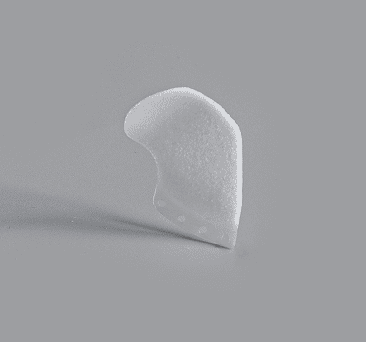

Enophtalmos Wedge